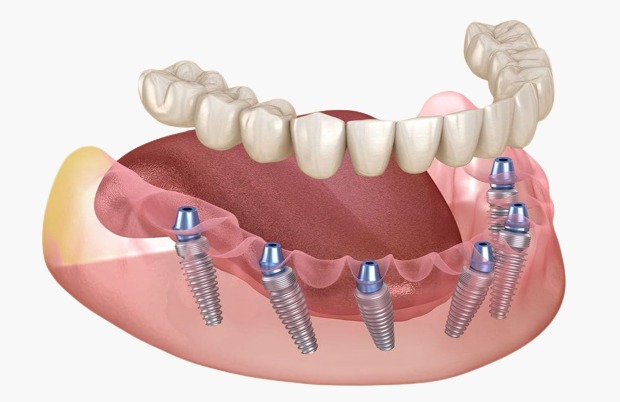

What are All-On-6 implants?

Implants are an innovative dental solution that enables the replacement of all teeth in one jaw using only six implants. The implants are placed so that they firmly support the entire bridge fixed on them, thus creating a firm and stable base for the new teeth.

Placement procedure for All-On-6 implants

The implant placement process usually involves several steps:

Implantation: Once approved, the surgeon will place six implants in the jaw during a simple surgical procedure.